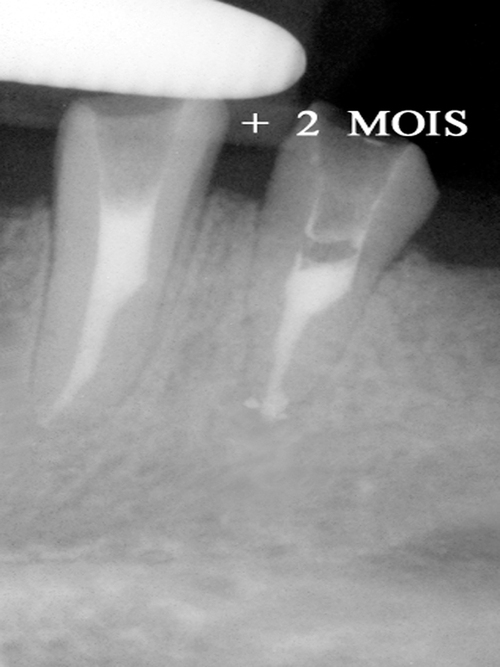

En cas d’infection sous une racine, il est possible de tenter la conservation de cette racine en supprimant cette infection (fig.15).

fig. 15

Infection péri apicale sur les deux piliers de bridge